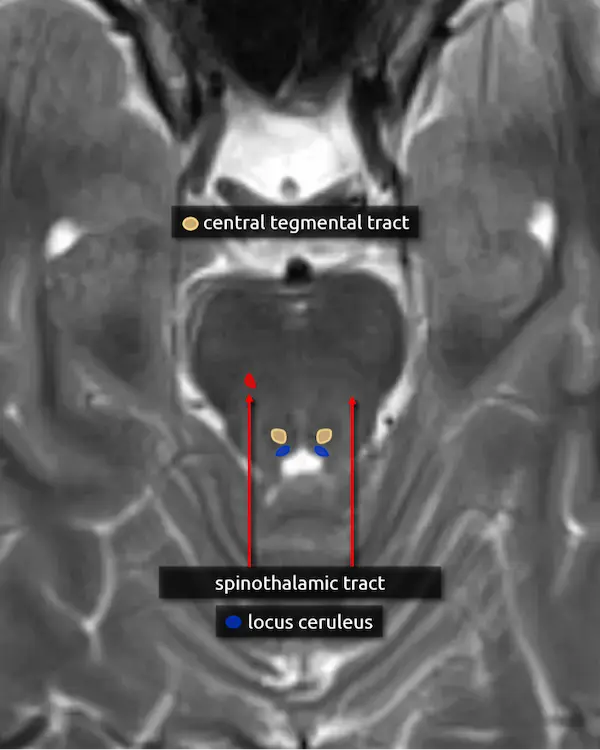

8. Locus ceruleus

The locus ceruleus is located in the posteromedial aspect of the upper pons and means "blue spot," named due to its pigmented appearance. It contains noradrenergic neurons responsible for producing norepinephrine. Additional noradrenergic neurons similar to those in the locus ceruleus are located in the lateral tegmentum of the pons and medulla (lateral tegmental area). Together, these regions supply norepinephrine to both the brain and spinal cord involved in a variety of functions, notably arousal, attention, and blood pressure control.

9. Central tegmental tract

The central tegmental tract extends from the midbrain to the medulla but is easiest to approximate in the dorsal pons. It connects the red nucleus to the ipsilateral inferior olivary nucleus (see the dentatorubro-olivary pathway).

Signal abnormalities of the central tegmental tract may occur with vigabatrin toxicity, which is common in children being treated for infantile spasms. Lesions here may also cause hypertrophic olivary degeneration, classically associated with palatal myoclonus.